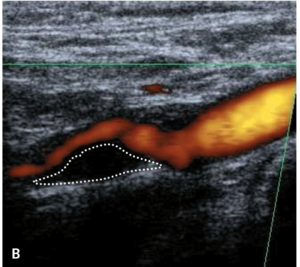

Badaniem ultrasonograficznym można uwidocznić zwężenie i ocenić jego morfologię.

Morfologia zmiany miażdżycowej nie stanowi według standardów kryterium kwalifikacyjnego do rewaskularyzacji, ale wykazuje silny związek z ryzykiem udaru niedokrwiennego mózgu zarówno u chorych leczonych zachowawczo, jak i okołozabiegowego IS w czasie rewaskularyzacji [18].

Zmiany hipoechogeniczne to zmiany częściej lipidowe lub skrzepliny, zmiany izoechogeniczne to zmiany włókniste, a zmiany hiperechogeniczne zawierają zwapnienia.

Zmiany hipoechogeniczne (skrzeplina, lipidowa) są związane z dużym ryzykiem IS zarówno u chorych dotychczas bezobjawowych, jak i w trakcie CAS czy endarterektomii (carotid endarterectomy, CEA), bo łatwo je uruchomić i rozkruszyć, powodując zatory do tętnic mózgowych [18].